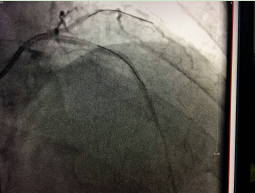

近日,我院成功应用切割球囊为一例冠脉内支架再狭窄的患者进行了冠脉内成形术,解除了患者胸闷胸痛症状。据了解,此项技术的开展在我市市属医院中尚属首次,该技术的开展为冠脉支架内再发狭窄的患者带来福音。 切割球囊 老人支架植入后再发心绞痛 冠脉内切割球囊成形术解决难题70多岁的周阿姨两年前因...